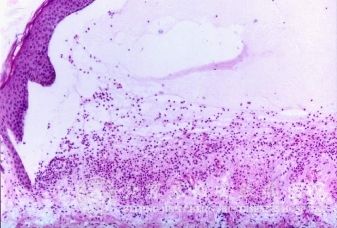

北京京城皮肤医院指出:自身敏感性皮炎发病机制尚不十分清楚。发病前常有接触性皮炎、钱币状湿疹等原发病灶,由于处理(使用刺激性药物、过度搔抓等),或并发化脓性感染而使原有损害恶化,出现红肿、糜烂、大量渗出,以致组织分解产物、细菌产物及外用药物等被吸收而形成一种自身抗原,从而引发变态反应性疾病。